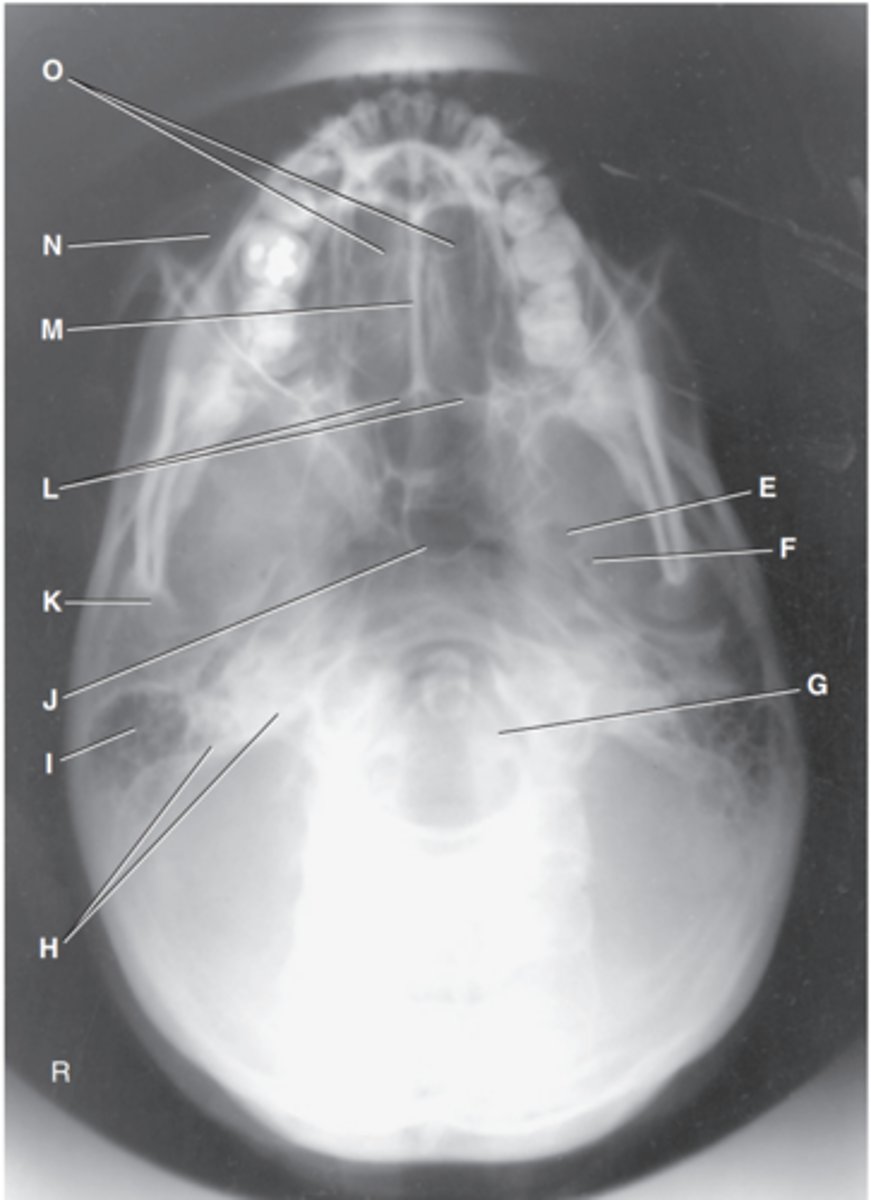

Foramen magnum

Label J

Zygomatic arch

Label A

Palatine process of maxilla

Label B

Horizontal process of palatine bone

Label C

Pterygoid hamulus of sphenoid

Label D

Foramen ovale of sphenoid

Label E

Foramen spinosum of sphenoid

Label F

Foramen magnum

Label G

Petrous pyramid of temporal bone

Label H

Mastoid portion of temporal bone

Label I

Sphenoid sinus in body of sphenoid

Label J

Condyle of mandible

Label K

Posterior border of palatine bone

Label L

Vomer

Label M